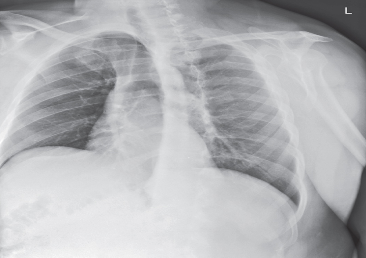

PA evaluation criteria

entire lungs included

no rotation

scapulae removed from lungs

chin elevated

full inspiration

equal collimation top and bottom

no motion

exposure factors

marker

hilum region markings

heart

great vessels

bony thorax